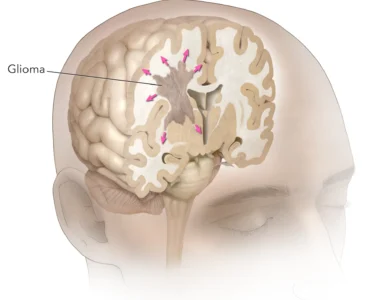

Brain Tumor: Early Diagnosis Saves Lives! 🧠🛡️

Don`t ignore the warning signs—timely action can save brain function.

A brain tumor is a serious condition, but early detection makes all the difference. As we say: "دماغی رسولی کا بروقت علاج زندگی بچا سکتا ہے" (Timely treatment of a brain tumor can save a life).

🚨 Common Symptoms to Watch For:

Persistent Headaches: Unexplained or worsening head pain.

Vision Issues: Blurred vision or sudden changes in eyesight.

Seizures: New onset of seizures or convulsions.

Vomiting: Frequent nausea or vomiting not related to other illnesses.

Limb Weakness: Numbness or loss of strength in arms or legs.

Speech Problems: Sudden slurred speech or difficulty communicating.

Personality Changes: Shifts in mood, behavior, or self-identity.

Confusion: Feeling disoriented or struggling with cognitive tasks.

If you or a loved one are experiencing these symptoms, consult our specialists immediately. Early diagnosis is your best defense.